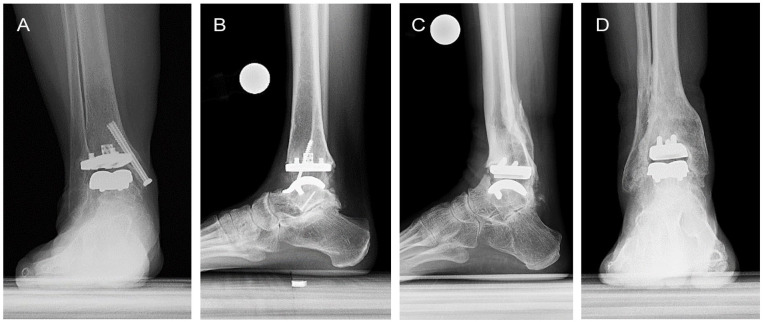

Results: TAR was performed a mean of 5.3 ± 3.5 years following distraction arthroplasty. At mean 4.4-year follow-up after TAR, 18/19 (94.7%) ankles remained implanted. One ankle was revised because of failure of the talar component, and there were 4 additional reoperations. Radiographic complications were observed in 37% of patients at 2 years postoperatively. Patients experienced significant improvement at 2-year follow-up for PROMIS domains of Physical Function (P = .002), Pain Interference (P = .007), and Pain Intensity (P = .010). At final follow-up, PASS was achieved by 65% and 71% of patients in the Physical Function and Pain Interference domains, respectively, but only 35% in the Pain Intensity domain.